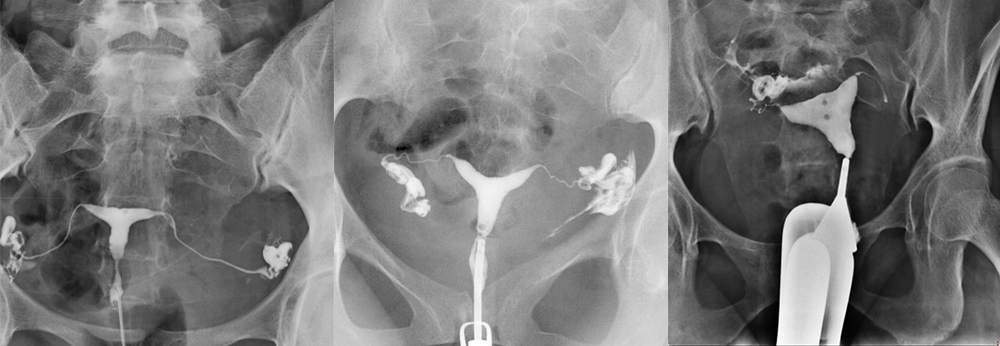

Rahim filmi, tıbbi adıyla “histerosalpingografi”, rahim boşluğu ve fallop tüplerinin röntgen altında görüntülenmesini sağlayan bir tanı yöntemidir. Genellikle çocuk sahibi olamayan kadınlarda tüplerin tıkalı olup olmadığını belirlemek, rahim içindeki yapısal problemleri görmek için uygulanır. Rahim içine özel bir sıvı verilerek çekilen bu film, üreme sağlığı açısından önemli bilgiler sunar.

HSG filmi ile tüplerin açık olup olmadığı, rahimde polip, miyom, yapışıklık veya şekil bozuklukları gibi sorunlar tespit edilebilir. Ayrıca tüplerin uç kısmında sıvı birikimi olup olmadığı da bu yöntemle görülebilir. Tüm bu bilgiler, kısırlık nedenlerinin belirlenmesinde ve doğru tedavi planının yapılmasında kritik rol oynar.